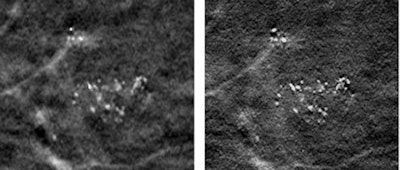

The researchers also compared two breast images taken with the Selenia Dimensions and created in different ways: using voxels that match the detector element size (140 µm); and using a back-projection filtered reconstruction with 35-µm voxels.

| Left: Image created by bilinearly interpolating a conventional reconstruction using 140-µm voxels; the net result has 35-µm voxels. Right: Image created by a back-projection filtered reconstruction with 35-µm voxels; this image displays the microcalcification morphology more clearly. Images courtesy of medicalphysicsweb. |

"You can see microcalcification structural features more clearly in the super-resolution image, and can also see some microcalcifications that you can't see on the other image," Acciavatti explained. "Having a clearer picture of the shape of a microcalcification provides useful diagnostic information."